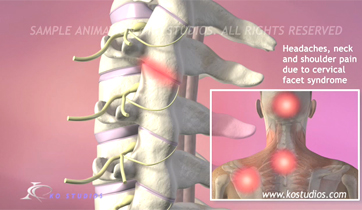

Cervical Facet Syndrome and Rhizotomy

Courtroom Animation for Law firm

This animation was created to be used as demonstrative evidence in a personal injury case. Visual aids such as this can help the jury understand complex medical injuries and procedures. We can customize each animation to be case specific.